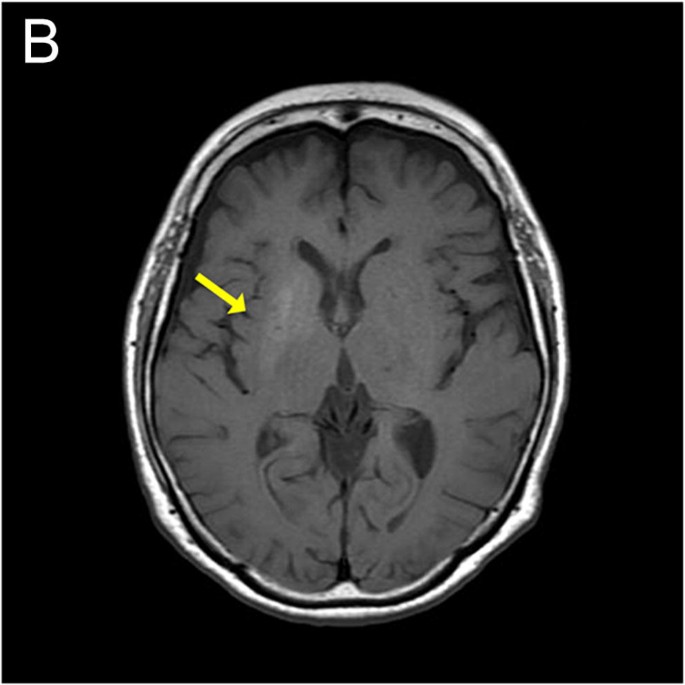

Diagnosis: Primarily diagnosed using brain MRI, which typically shows high-signal intensity (hyperintensity) on T1-weighted imaging in the basal ganglia (specifically the putamen).